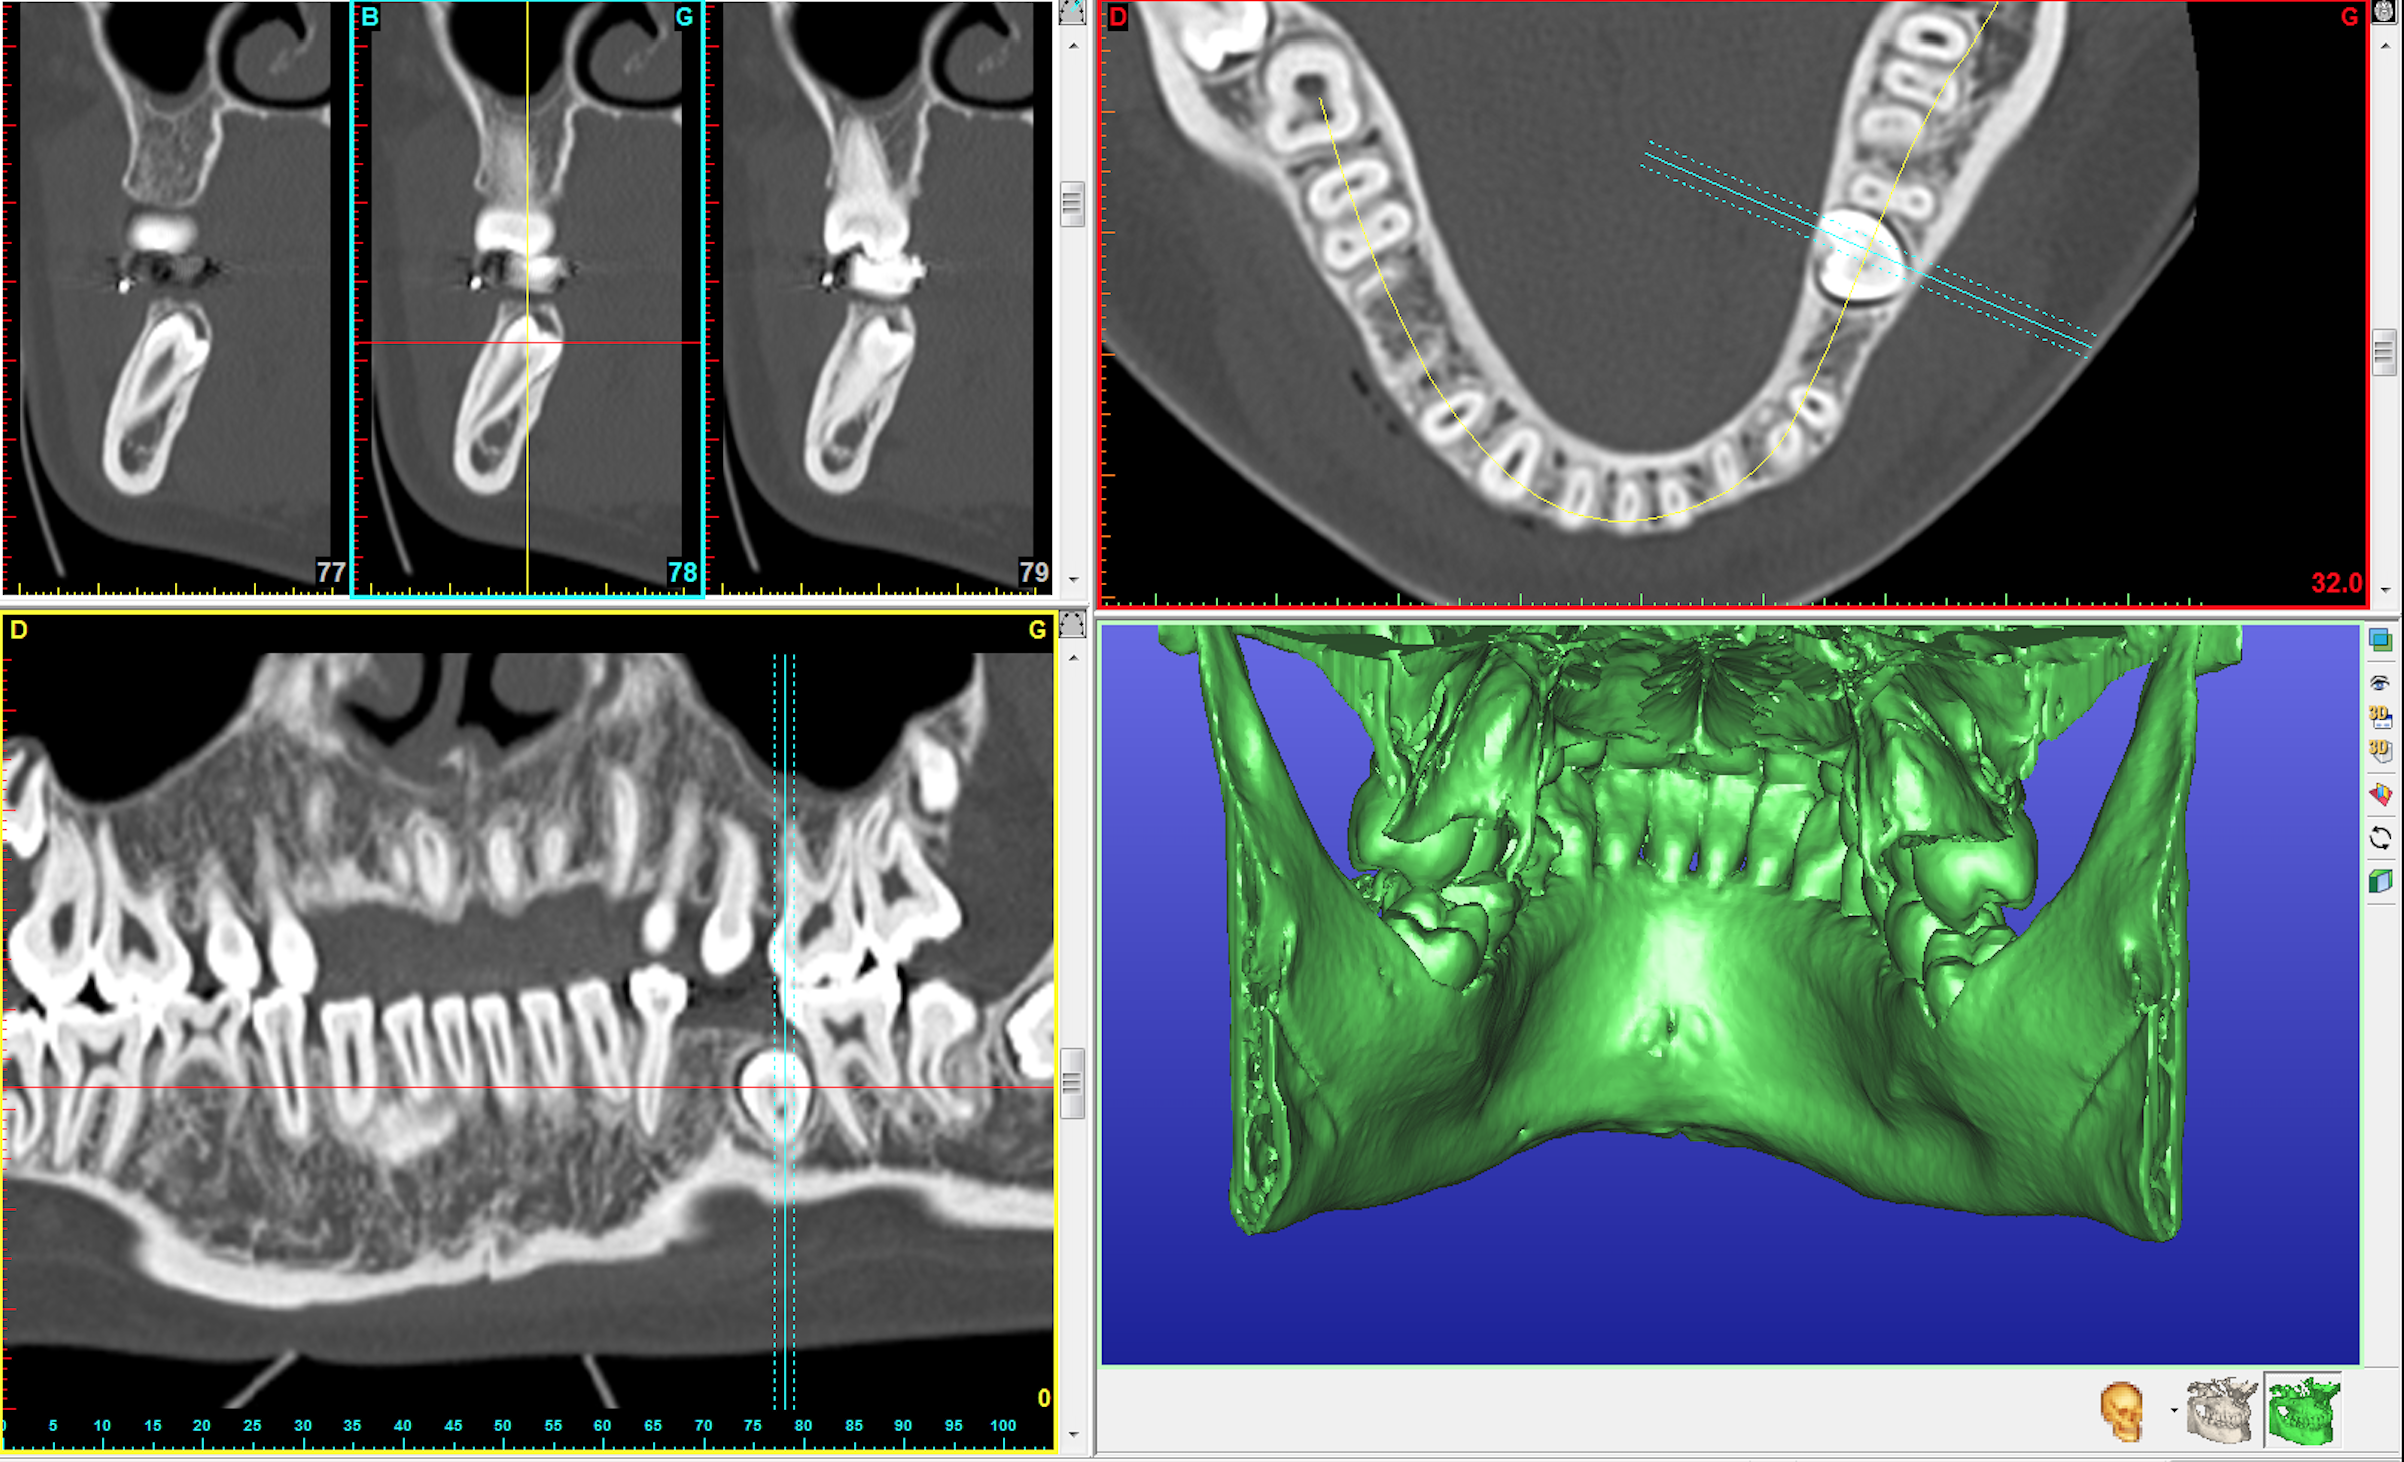

L’extraction des dents de sagesse consiste à enlever les troisièmes molaires du haut et/ou du bas. Chez l’enfant ou l’adolescent, ces dents n’ont pas terminé leur développement et sont appelés germes (l’intervention est appelée « germectomie »).

Ces dents doivent être extraites parce qu’elles sont en mauvaise position et sont à l’origine de douleurs et d’inflammation ou parce qu’elles risquent de perturber le bon alignement des dents chez l’enfant ou l’adolescent (l’indication est souvent portée par l’orthodontiste) .

• une diminution ou une modification de la sensibilité de la lèvre inférieure ou plus rarement de la langue car les nerfs cheminent à proximité de la dent et peuvent être irrités. Ce trouble de la sensibilité est temporaire (quelques jours à quelques semaines), mais dans certains cas, la récupération peut être très longue (1 à 2 ans). Ce trouble est très exceptionnellement permanent.

• une communication entre le sinus maxillaire et la bouche pour les dents supérieures, qui se ferme spontanément en 15 jours à 3 semaines. Une persistance au-delà justifie un traitement chirurgical adapté.

• l’expulsion de la dent de sagesse supérieure en haut dans le sinus maxillaire ou en arrière de celui-ci est très rare mais peut justifier une nouvelle intervention chirurgicale pour la récupérer.